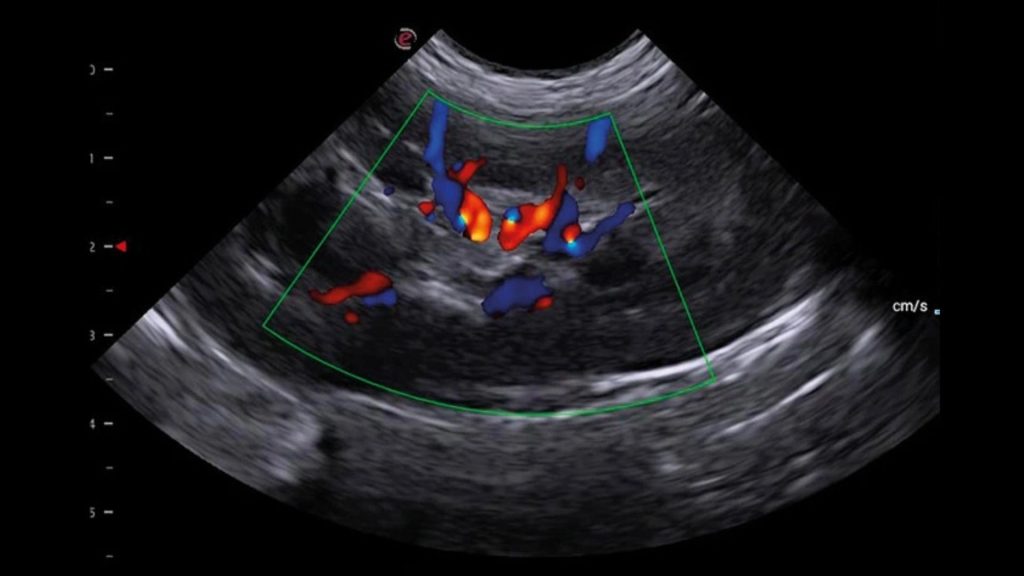

Kedi ve köpeklerde, portal sistem, caudal vena cava, aorta ve iliak damarların trombus ve embolileri ultrasonografi ile tespit edilebilir. Aortik ve iliak tromboembolizm, kedilerde kardiyomiyopatiyle birlikte ortaya çıkan önemli bir komplikasyondur. Köpeklerde Aortik ve iliak tromboembolizm, genellikle hiperkoagülasyon durumlarıyla birlikte, kardiyak hastalık ve neoplazmalarla ilişkili bir hastalık olarak ortaya çıkar. Kedi ve köpeklerde, portosistemik şantlar dışında, abdominal vasküler malformasyonlarla nadiren karşılaşılır.

Karaciğer ultrasonografisinde, hepatik parankim (karaciğer dokusu), büyük hepatik ve portal damarlar, bitişiğinde caudal vena cava ve safra kesesi ve bilier sistem incelenir. Radyografiden farklı olarak ultrasonografi, hedef yapıların çeşitli düzlemlerden görüntülenmesine olanak sağlar. Karaciğerin ultrasonografik muayenesi sırasında hekimin tercihine göre hasta sağ yan, sol yan veya sırt üstü pozisyonlarında yatabilir. Daha iyi görüntü alınabilmesi için karın bölgesi göğüs bölgesine kadar tıraşlanıp temizlenmelidir. Görüntü kalitesini hastanın vücut yapısı, karaciğerin boyutu ve gastrointestinal içerik etkileyebilir. Mide içeriğindeki gaz iyi bir karaciğer görüntülemesinin önündeki en önemli engeldir. Bu sebeple hastanın aç olarak muayene getirilmesi tercih edilir. Karaciğer ultrasonografisine ihtiyaç duyulan durumlar, karaciğer hastalıklarıyla ilişkili klinik belirtiler (kusma, ishal, abdomende genişleme, abdomenin elle muayenesinde karaciğer boyutunun arttığının farkedilmesi vs.), laboratuvar analizlerinde biyokimyasal değişiklikler (ALT, ALP, AST, NH3, GGT, BİLİRUBİN, TOTAL PROTEİN, ALBUMIN), ikterus (sarılık), hepatomegali, asites, akut abdomen veya abdominal kitle şüphesi, metastatik kitle şüphesi, hepatik enseflaopati, immun sistem hastalıklarını içermektedir. Hepatik arterleri ve intrahepatik dallarını görüntülemek için Doppler muayenesi gereklidir. Doppler ultrasonografi ile hepatik arter, portal ven ve caudal vena cava incelenebilir. Konjenital veya edinsel Portasistemik Şantla (PSŞ) ilişkili klinik veya laboratuvar belirtileri olan hayvanlarda intrahepatik veya ekstrahepatik anormal damarlar da saptanabilir. Doppler görüntüleme ile aynı zamanda intrahepatik portal hipertansiyonun da tanısı konulabilmektedir.

Veteriner hekimlerimize ve sevimli dostlarımıza merkezimiz bünyesinde vermiş olduğumuz Veteriner USG hizmetimizde Esaote MyLAB X8VET Üst Düzey Renkli Doppler Ultrasonografi Cihazı ile hizmet vermekteyiz. Cihaz ile yapılan sonografik ve doppler çalışmalarında her türlü patolojilerde yüksek çözünürlükte görüntüleme imkanı sağlanmaktadır. İçerdiği yazılımlar ile tanıyı detaylandırarak teşhise götüren götürmeye yardımcı olmaktadır. Çoklu modalite aracı ile, hızlı bir tanıya ulaşmak için gerçek zamanlı ultrason görüntülemeyi çok çeşitli ikinci görüntüleme modaliteleriyle (MRI, CT, 3D Görüntüleme, Doppler) birleştirmek mümkündür.